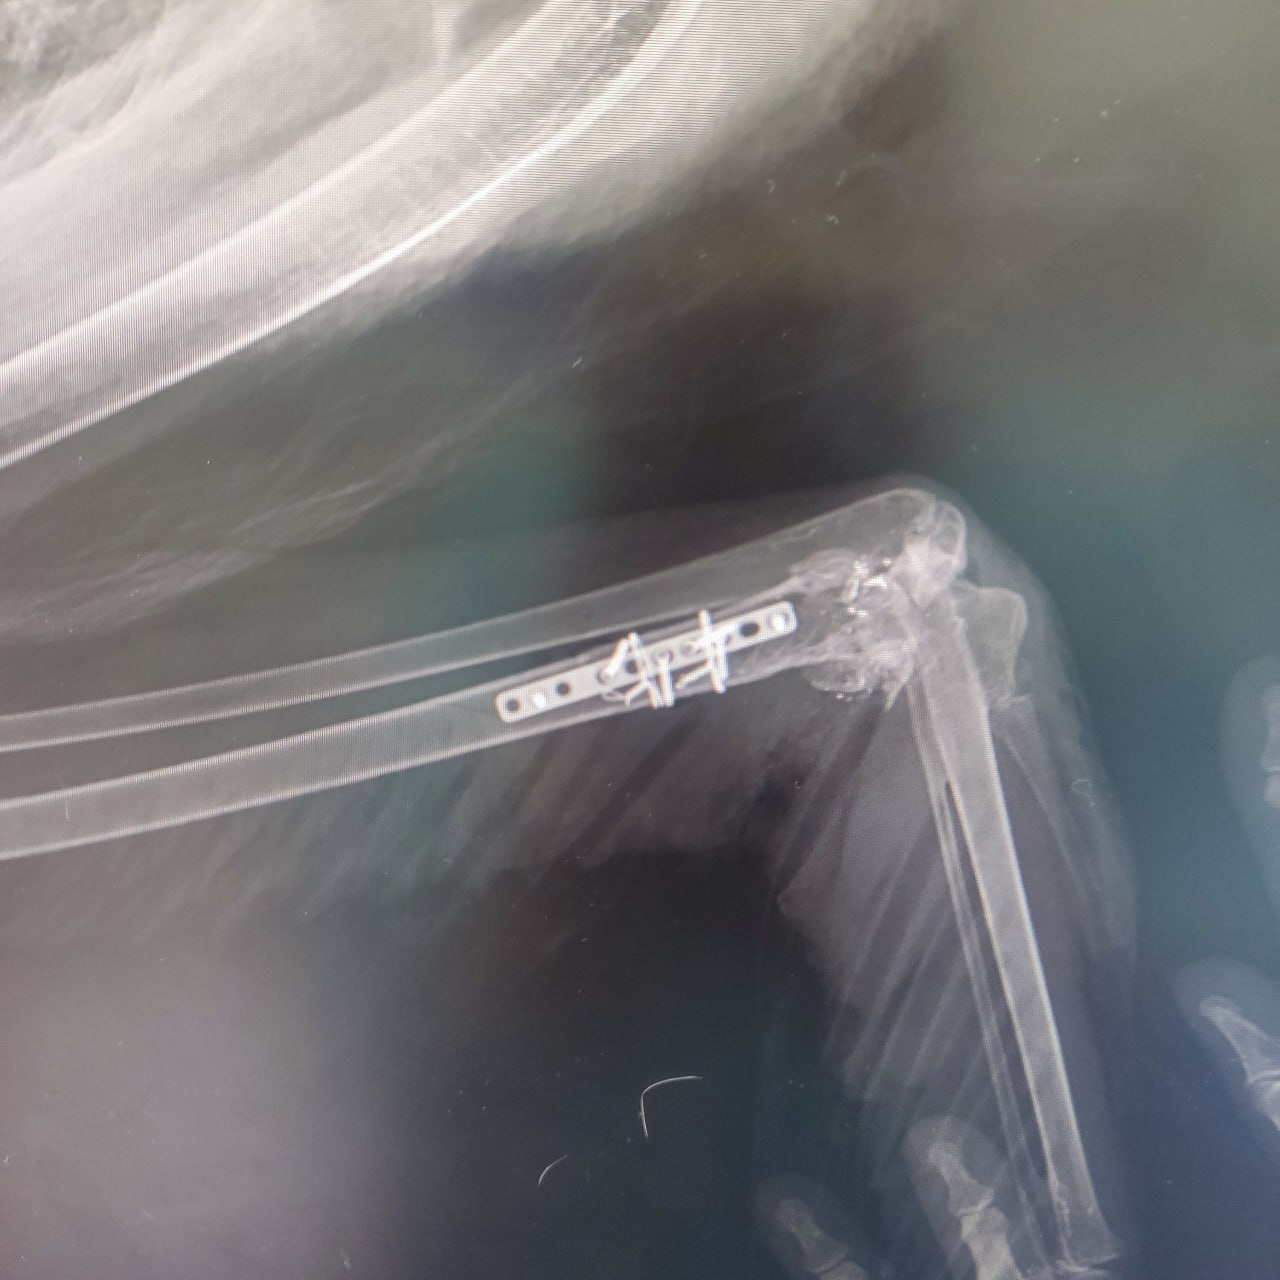

«У ребенка врожденная патология, либо перелом обоих крыльев — непонятно. Второе — он очень маленький для своего возраста», — отметили специалисты.